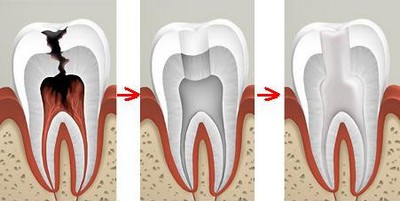

Чтобы терапия была действенной, специалист должен выполнить определённые процедуры:

- Полностью удалить некротизированную пульпу из корневых каналов.

- Механически расширить и очистить проходы.

- Провести обработку корневого канала и очага воспаления медикаментозными средствами.

- Полностью запломбировать корневой проход.

- Контролировать свои действия с помощью рентгена.

- Вскрывает канал.

- Удаляет некротизированную пульпу.

- Осуществляет прохождение канала зуба, его расширение и санацию.

- Воздействует с помощью лекарств на периодонтальные ткани.

- Пломбирует.

- Устраняет остаточные явления кариеса.